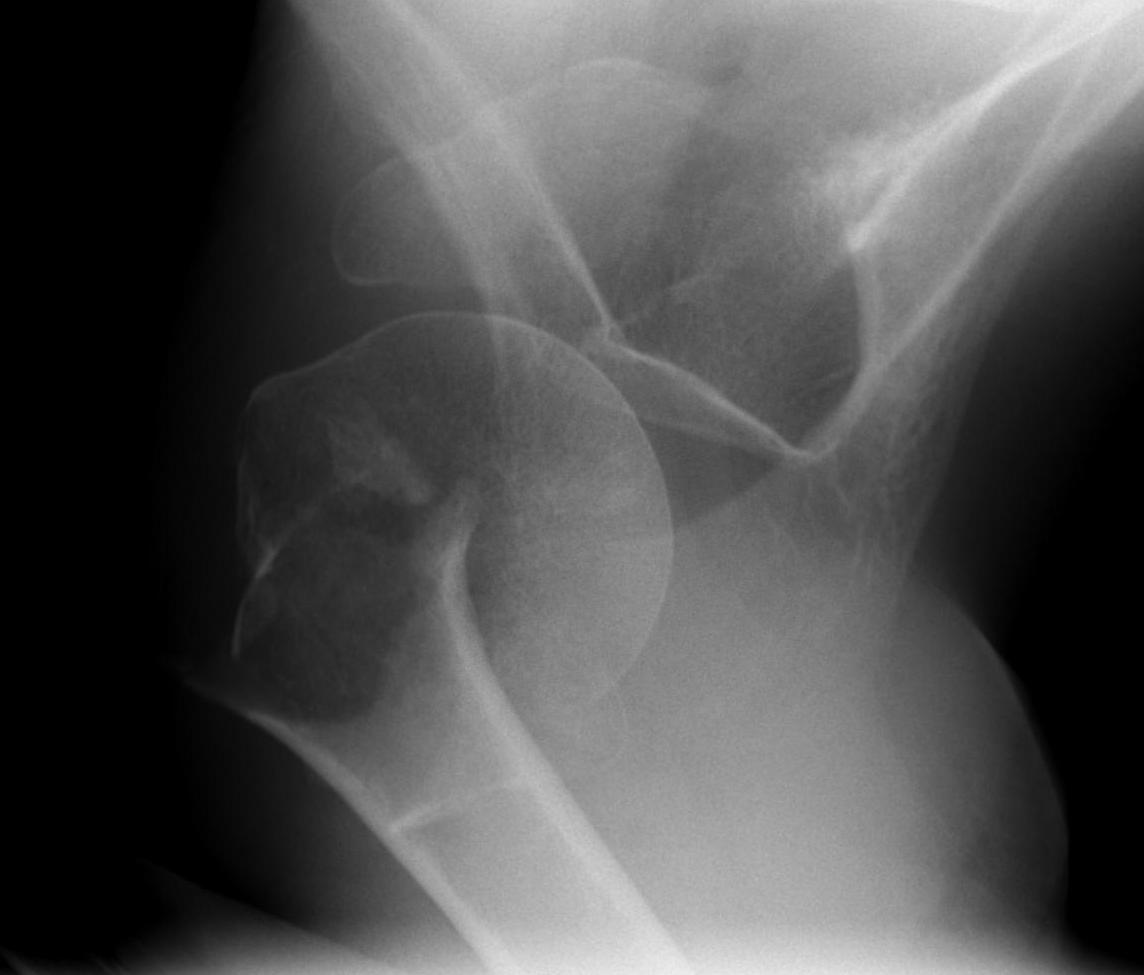

proximal humerus fracture Background ORIF with locking plate Arthroplasty Greater tuberosity fractures Lesser tuberosity fractures / avulsions Book traversal links for Proximal humerus fractures ‹ Pectoralis Major Tears Up Background ›